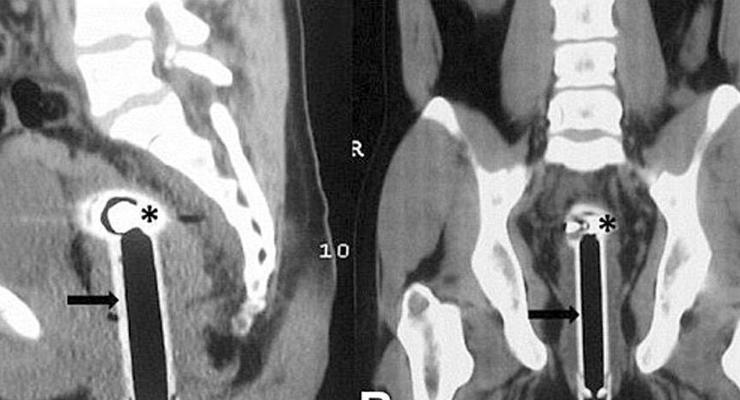

Hindistan’da 26 yaşında ismi açıklanmayan bir adam, banyoda kayarak duş başlığının üzerine düştüğünü söyleyerek hastaneye gitti. Doktorların yaptığı incelemeler sonucunda, duş başlığının adamın rektumundan 15 santimetre kadar içeri girdiği tespit edildi.

Başarılı bir operasyon geçirdiği açıklanan adamın sağlık durumunun iyi olduğu ifade edildi.

Konuyla ilgili açıklamalarda bulunan doktorlar, adamın hikayesinin inandırıcı gelmediği ve ‘muhtemelen’ yaşanan olayın ‘kaza olmadığı’ yönünde görüş belirtti.